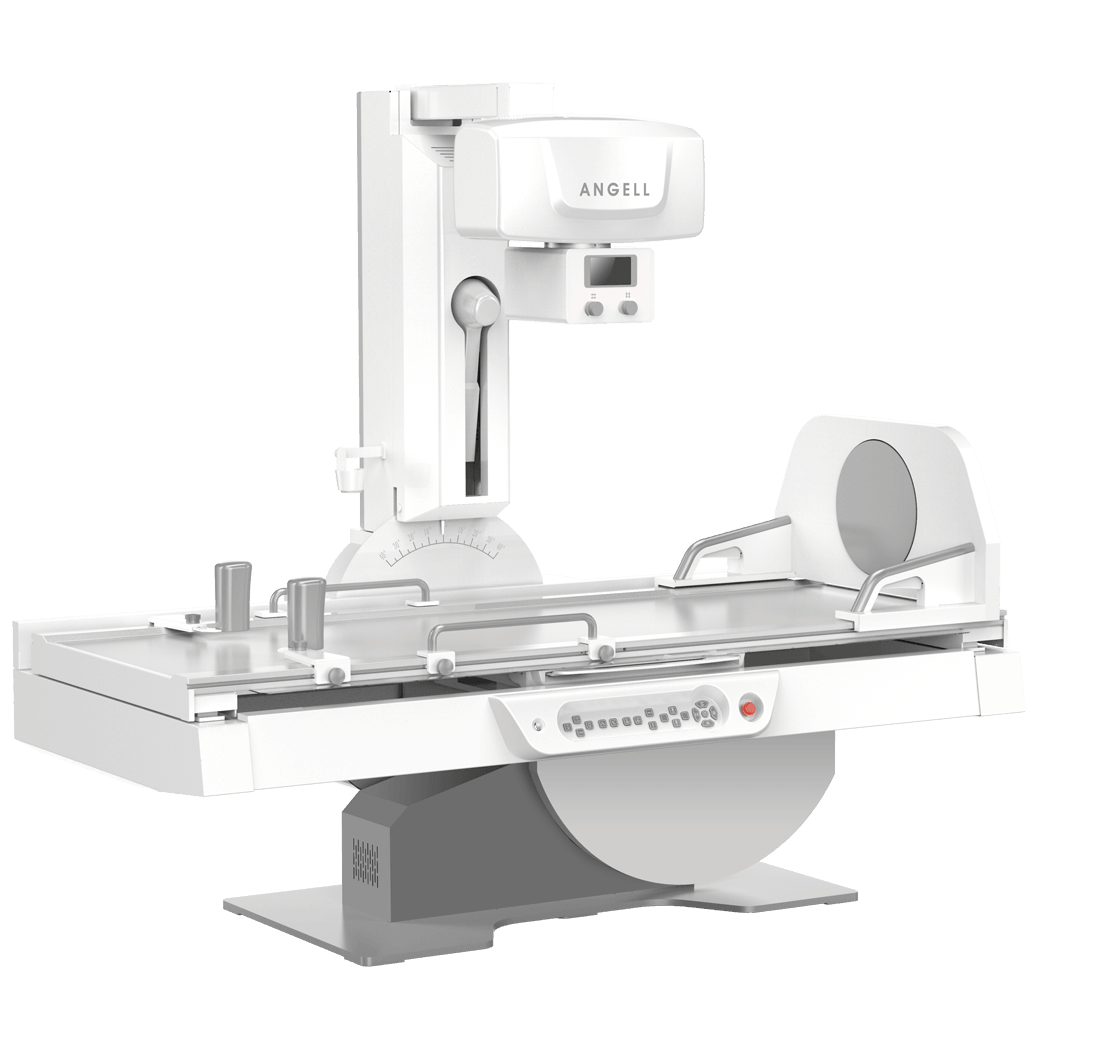

腾灵系列

多功能诊断专用动态DR

太阳成集团tyc122cc入口科技全新设计的第四代床式动态DR,集拍片、透视、造影、全身拼接、尘肺体检于一体,一机多能,真正意义上实现全科室应用,提升医院实际效益。

多功能诊断应用专业设计

从医疗机构放射科的实际应用出发,针对多功能诊断进行多维度专业设计,优化病人检查体验,大幅提升操作技师工作效率。

多功能专用结构设计

轻松满足各种角度投照及尘肺检查需求 -

超低床体设计

病人轻松上下床 -

旋转脚踏设计

医生可轻松便捷遥控病人转体,提升一倍查体效率 -

一体化操控台设计

集成化操控台,支持系统一键开关机,支持医生双手协同操控 -

可移除式滤线栅设计

有效满足妇科儿科检查时的低剂量要求 -

升降型移动操控台设计

升降式设计保障不同高度的操作舒适度,支持医生进行床边操控、曝光及观察